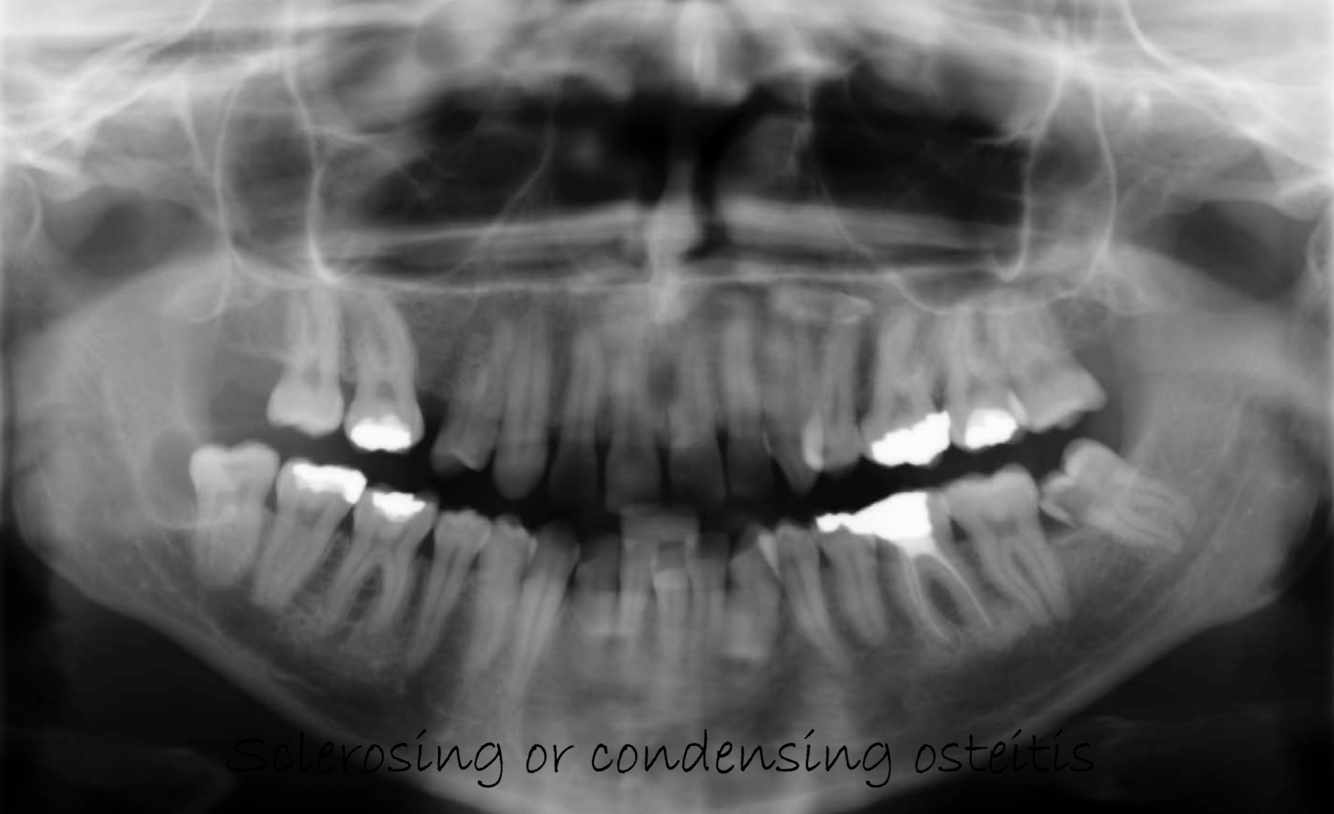

What can be seen in Chronic inflammation - long standing?

Circumscribed, well defined, radiolucent area periapically with sclerotic bone surrounding

radiolucency sometimes described as rarefying osteitis

Multiple radiolucencies enhance appearance of IDC

Chronic root resorbtion

Radicular cyst